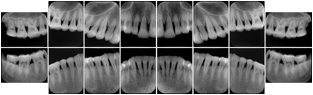

In most standard cases, images are oriented in structured layouts. These structured displays are useful to be shared between providers for reference purposes.

Table OO.1.1-1 shows structured display standard templates, where Viewset ID is based on the Japanese Society for Oral and Maxillofacial Radiology (JSOMR) classification provided by JIRA (Japan Medical Imaging and Radiological Systems Industries Association, www.jira-net.or.jp). Expected or typical teeth to be imaged location, region and designation codes are based on ISO 3950-2010, Dentistry - Designation system for teeth and areas of the oral cavity. For all the hanging protocols listed in OO.1.1-1, the value to use for Hanging Protocol Creator (0072,0008) is "JSOMR" and the value to use for Hanging Protocol Name (0072,0002) does not include "JSOMR" (e.g., "DL-S001A", not "JSOMR DL-S001A").

Table OO.1.1-1. Hanging Protocol Names for Dental Image Layout based on JSOMR classification